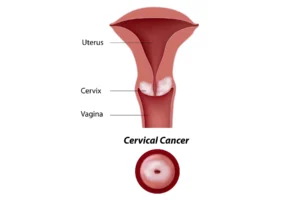

Cervical Cancer

PET scans in cervical cancer are used to detect the primary tumor in the cervix, evaluate lymph node involvement, and identify metastases. It provides detailed images that help in staging the disease, guiding biopsies, and planning radiation therapy.